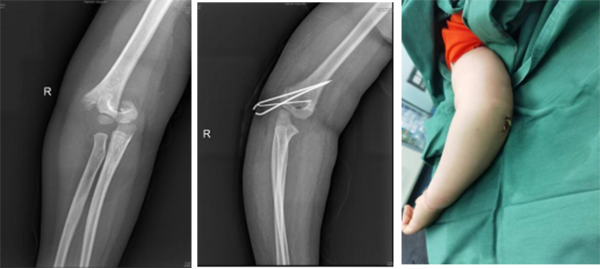

徐醫(yī)附院小兒骨科依托省級(jí)臨床重點(diǎn)?乒强破脚_(tái),擁有雄厚的醫(yī)療、科研實(shí)力,配備了脊柱手術(shù)顯微鏡、術(shù)中導(dǎo)航、脊柱微創(chuàng)內(nèi)鏡、關(guān)節(jié)鏡設(shè)備、術(shù)中神經(jīng)電生理監(jiān)測(cè)、超聲骨刀等先進(jìn)設(shè)備,極大地保證了患兒高難手術(shù)的精準(zhǔn)性和安全性。自2022年2月17日成立以來,徐醫(yī)附院小兒骨科秉承“微創(chuàng)化、精準(zhǔn)化”的治療原則,為淮海經(jīng)濟(jì)區(qū)兒童骨科患者提供優(yōu)質(zhì)的醫(yī)療服務(wù),贏得了廣泛贊譽(yù)。當(dāng)前,徐醫(yī)附院小兒骨科每月完成手術(shù)近40余臺(tái)。小兒肱骨髁上骨折、前臂骨折、股骨干骨折等常見骨折基本上都是經(jīng)皮微創(chuàng)完成,獲得患兒家長(zhǎng)的好評(píng)和信任。